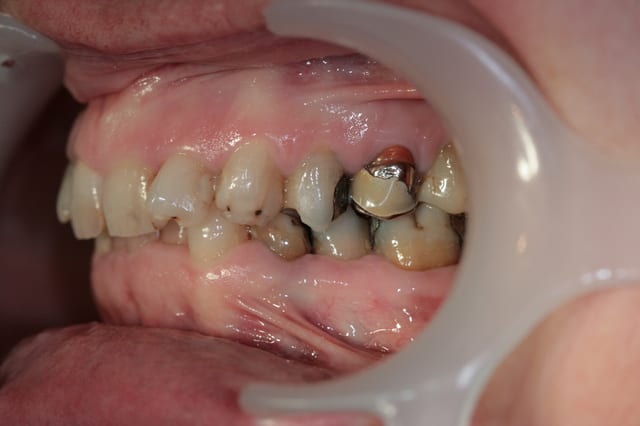

Récemment Céramik râlé, parce qu'il n'y avait pas de nouveau cas (esthétique je crois) à se mettre sous la dent. Je me jettes à l'eau avec ce dernier cas posé ce vendredi (y'a pas plus frais), une larme à l'oeil parce qu'il s'agit aussi du dernier gros cas dans mon cabinet que je quitte cette semaine pour rejoindre ma belle et nos p'tits bouts loin la bas dans le sud.

La patiente a un sourire très médiocre avec migration de plus en plus marqué du bloc incisivocanin sup. Comment l'aidez vous?